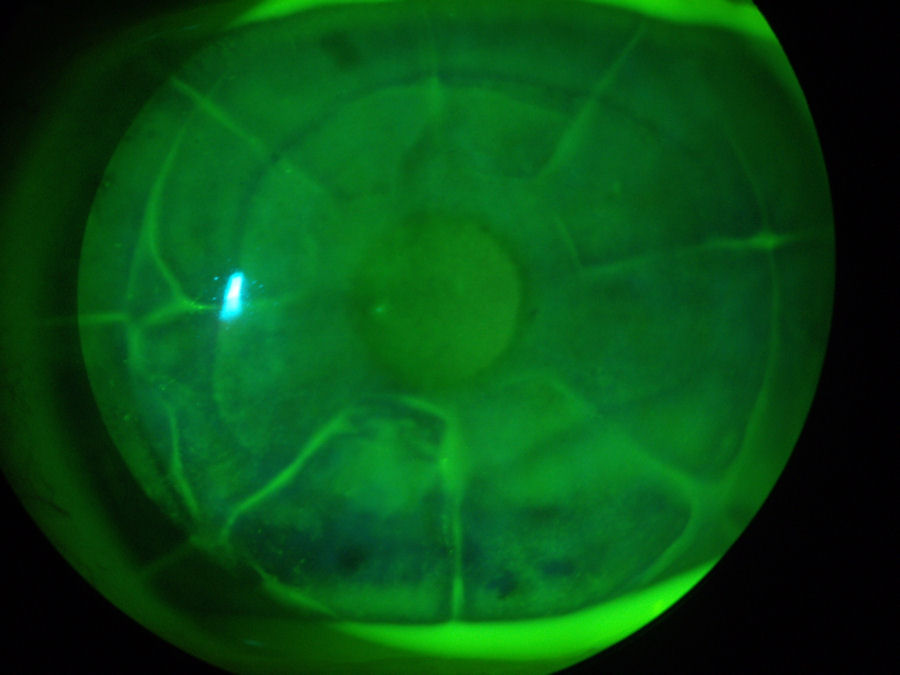

КК был введен для лечения дальнозоркости. КК использует иглоподобный зонд для доставки радиочастотной энергии (тепла) к коллагену периферической части роговицы в кольце индивидуально расположенных точек. Нагревание приводит к сокращению коллагена роговицы, что приводит к утолщению центральной части роговицы. Ниже вы можете четко видеть восемь точек, расположенных кольцом вокруг роговицы, в которые были введены зонды для КФК. Красная стрелка указывает на одно из мест КФК. Сразу за кольцом СК-пятен находится край лоскута LASIK, обозначенный белой стрелкой. Такие повреждения роговицы никогда полностью не заживают.